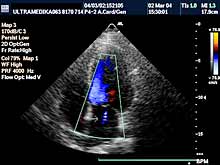

Najčešći simptomi: Indikacije su

obično ultrazvučna procena kardiovaskularnog statusa.

Pregled podrazumeva obaveznu primenu:

- Broadband-CD,

- TDI,

- pulsni i kontinuirani dopler.

Pregled vrši kardiolog.